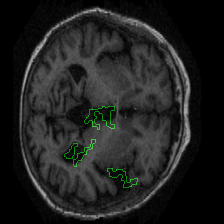

Figure 1 presents attribution maps generated using PWIG for a selection of MRI scans across all four diagnostic categories. The highlighted regions (in green) correspond to the areas that contributed most significantly to the model’s decision. Notably, we observe consistent emphasis on anatomical structures that align with clinical markers of dementia, including cortical and subcortical regions. For instance, in the moderate and mild dementia examples, the model focuses on regions exhibiting visible atrophy or abnormal morphology. In contrast, attribution maps for non-demented subjects appear more diffuse and less concentrated, reflecting the model’s detection of normal anatomical patterns.

The results in Figure 1 demonstrate that PWIG can effectively produce interpretable and clinically meaningful explanations for model predictions in medical imaging tasks.

Figure 1: PWIG attribution maps across dementia categories using the OASIS-1 dataset. Green overlays indicate regions with the highest attribution scores.